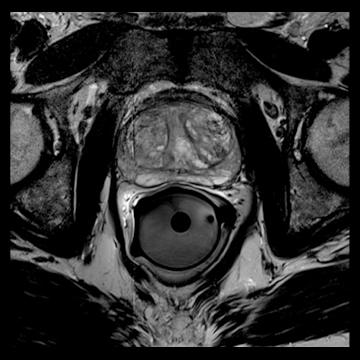

前立腺

高分解能T2

T2

RESOLVE, b=800

and ADC map,